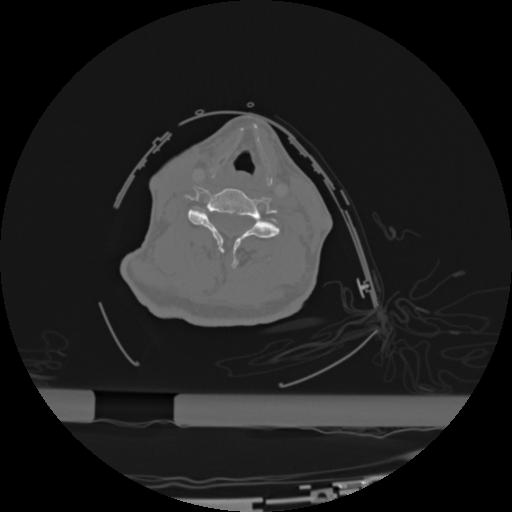

22 ANGIO,CE,Vol,0.5,ANGIO,,